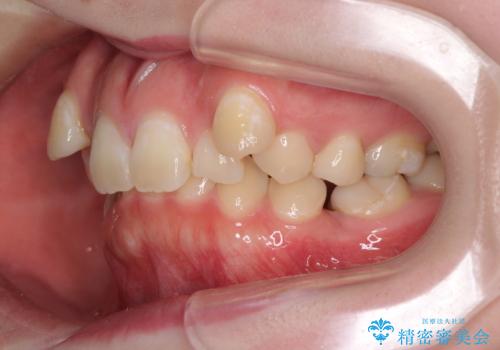

- 八重歯と下顎小臼歯の欠損を気にして来院された患者様です。

下顎小臼歯の欠損により過蓋咬合となっていたため、下顎は臼歯を起こすことで咬み合わせを改善し、八重歯は第一小臼歯2本を抜歯し、補助装置を使用して速やかに改善することとしました。

著しい過蓋咬合の改善が必要であった割には、治療期間は2年強と標準的でした。